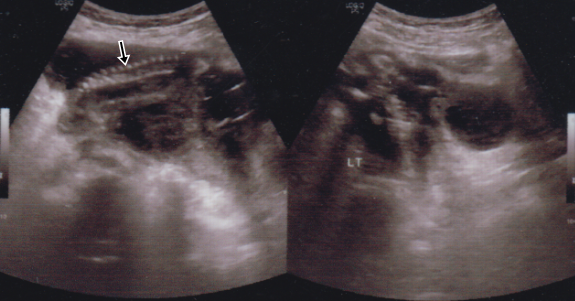

Imaging Of Cesarean Scar Ectopic Pregnancy. In The Ultrasonographic

Imaging of cesarean scar ectopic pregnancy. In the ultrasonographic www.researchgate.net